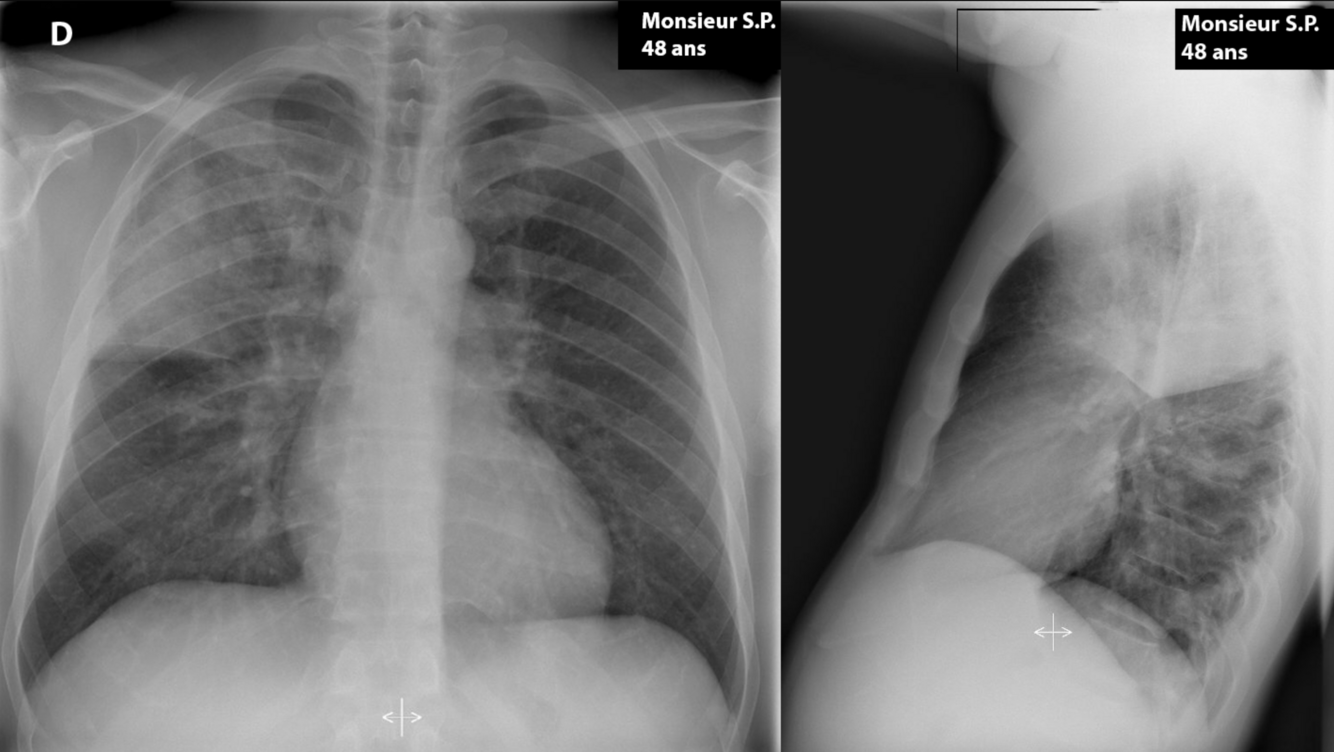

Monsieur S.P., 48 ans, fumeur, se présente à l’urgence pour toux et expectorations verdâtres depuis 48 heures. Il se plaint de forte fièvre et de frissons. Il ne prend aucun médicament et n’a pas d’allergie.

À l’examen physique:

TA 125/85, FC 130/min, RR 24/min, Saturation 95% AA

Température rectale 39,5°C

Poumons: crépitants de la portion supérieure du poumon droit (1/2 plage)

Le reste de l’examen physique est normal.

Quel est le diagnostic le plus probable?

A

Pneumonie du lobe supérieur droit

Infiltrat alvéolaire au lobe supérieur droit compatible avec une pneumonie acquise en communauté (PAC)